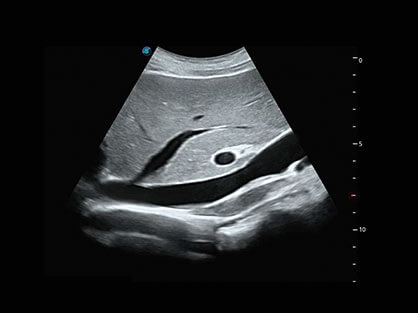

• 穿刺增强

自动识别穿刺针进行声束智能偏转 手动修正多档调节 提高一次穿刺成功率